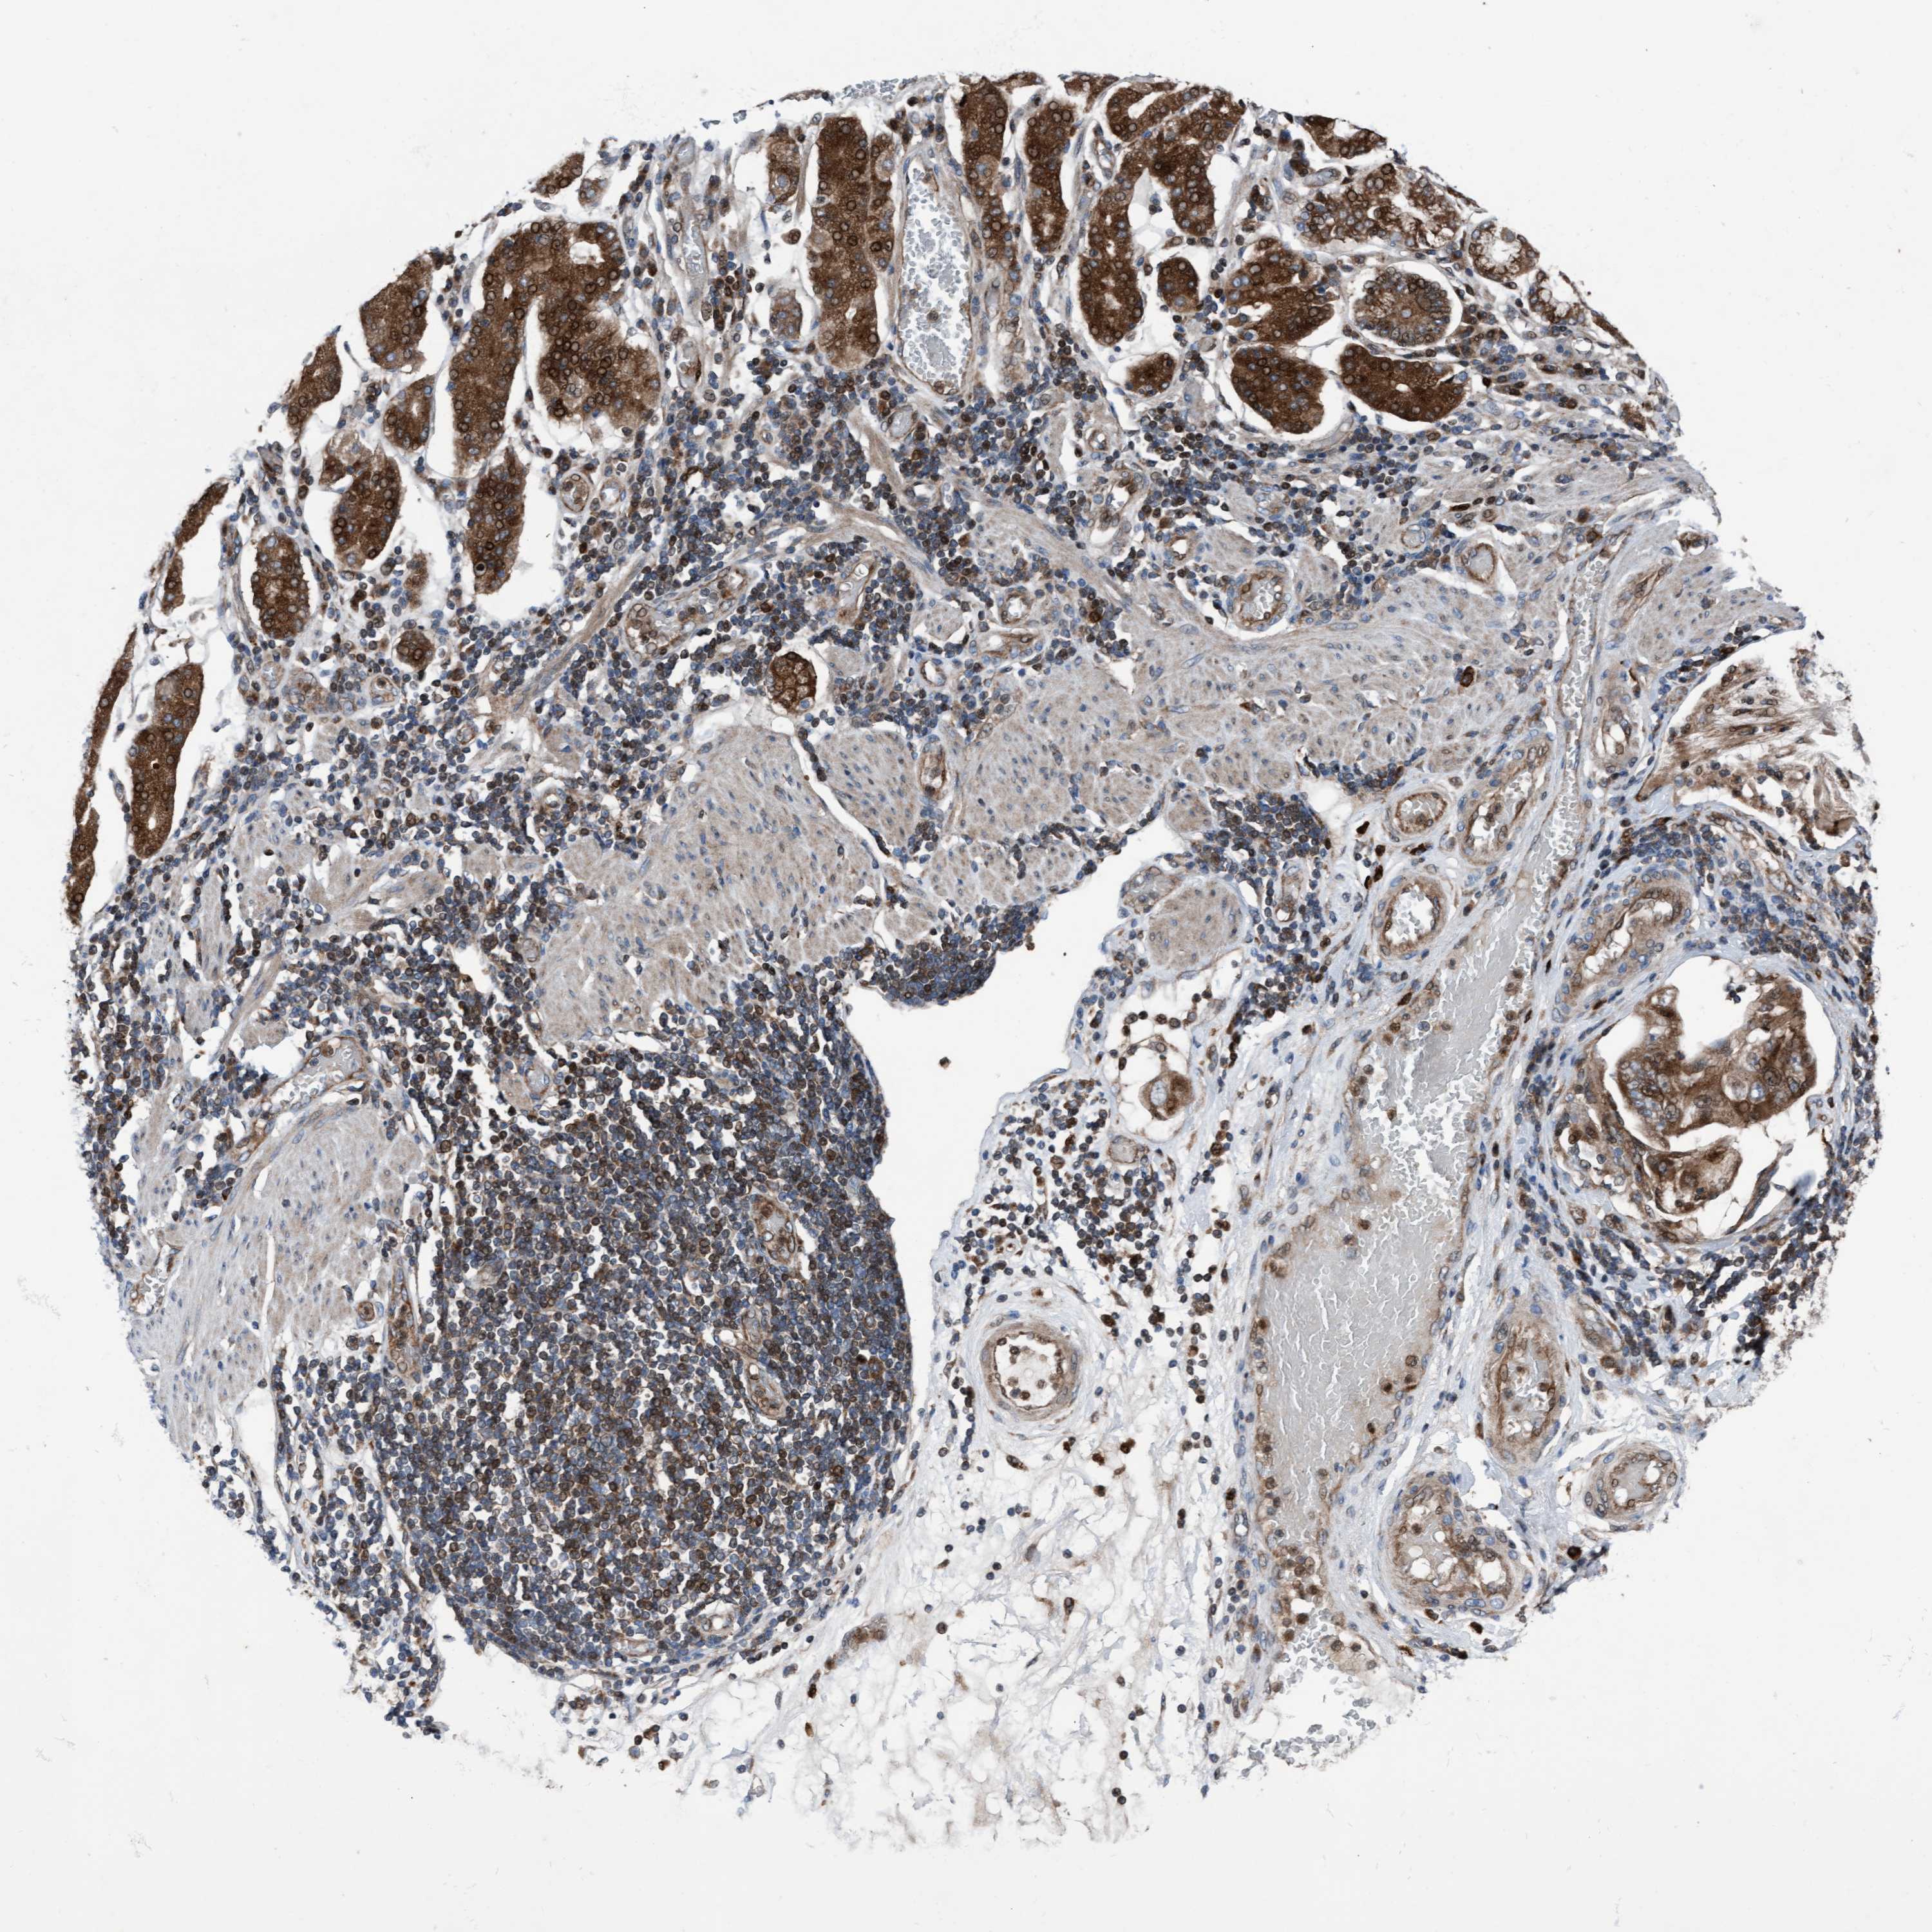

STOMACH CANCER - Protein expressioni

A mouse-over function shows sample information and annotation data. Click on an image to view it in a full screen mode. Samples can be filtered based on level of antibody staining by selecting one or several of the following categories: high, medium, low and not detected. The assay and annotation is described here.

Note that samples used for immunohistochemistry by the Human Protein Atlas do not correspond to samples in the TCGA dataset.

Antibody stainingi

Antibody staining in the annotated cell types in the current human tissue is reported as not detected, low, medium, or high, based on conventional immunohistochemistry profiling in selected tissues. This score is based on the combination of the staining intensity and fraction of stained cells.

Each image is clickable and will lead to virtual microscopy that enables deeper exploration of all samples and also displays staining intensity scores, fraction scores and subcellular localization as well as patient and tissue information for each sample.

Antibody HPA023074

Staining

High

Medium

Low

Not detected

Intensity

Strong

Moderate

Weak

Negative

Quantity

>75%

75%-25%

<25%

None

Location

Nuclear

Cytoplasmic/membranous

Cytoplasmic/membranous,nuclear

Adenocarcinoma, NOS